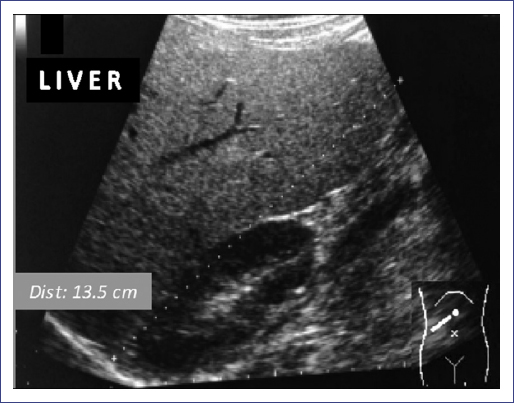

Hepatic ultrasound revealed hepatomegaly with fat deposition suggestive of moderate hepatic steatosis (Fig. 2) without splenomegaly. The family did not agree to perform a liver biopsy. No abnormal brain findings were shown by magnetic resonance imaging (Fig. 3). Thyroid gammagram with 131I and thyrotropin alpha stimulation (TSH = 43.26 mIU/l) was considered within the normal limits, and no data suggested residual thyroid tissue.

Figure 2 Hepatic ultrasound. The echogenicity of the liver was higher than that of the renal cortex, with intrahepatic vessels not well depicted.